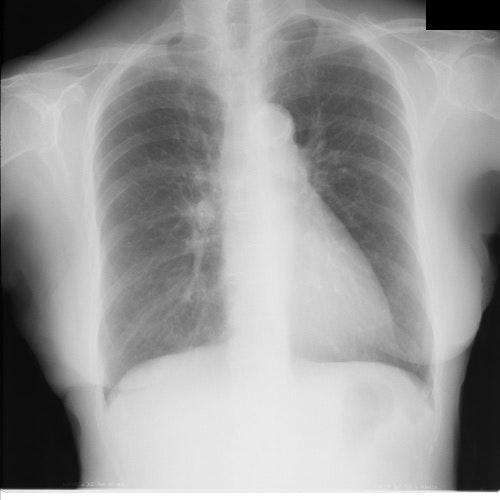

データを加工してみる

imgの全ての値を4096で割って256をかけてみます。

img2 = img / (mx + 1) * 256.0

import cv2

from PIL import Image as im

from IPython.display import display, Image

_, buf = cv2.imencode(".jpg", img2)

dat = Image(data=buf.tobytes())

display(dat)

できた!

この画像を使ってアノテーション作業を行なって、実際の処理は元の4096階調を使うようにして機械学習させればいいかも!